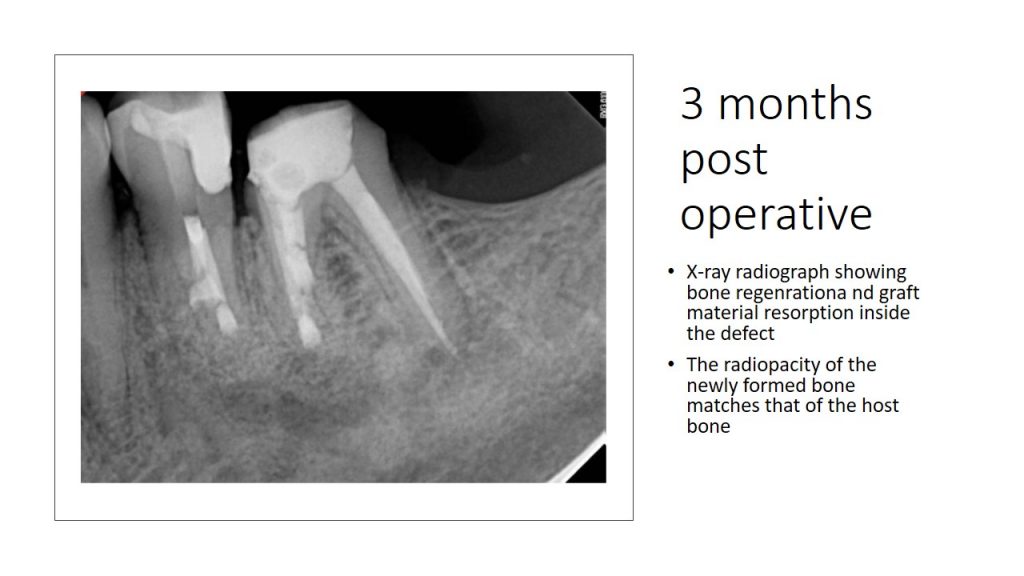

From shefabone.com

EndodonticsCase2Slide3 Shefa Bone Endodontic Cases In the present case report, we describe a geminated maxillary second molar tooth that underwent a successful root canal. Here, we report endodontic cases that had been misdiagnosed as skin or periodontal diseases. Stephen buchanan discusses approaching zero loss of structural integrity during rct mentioning the term “minimally invasive. Pridase 2024 guidelines for reporting diagnostic accuracy studies in endodontics: The. Endodontic Cases.